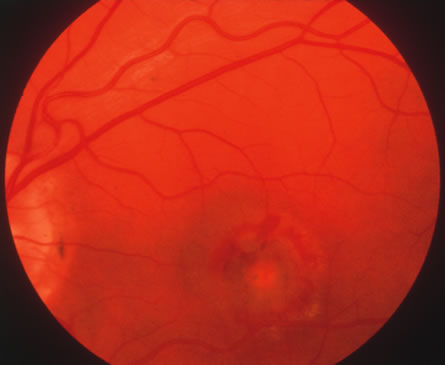

Ocular involvement occurs in fewer than 10% of patients with cat-scratch disease (Fig. 22).86 In addition to Parinaud's oculoglandular syndrome, other manifestations include neuroretinitis, focal or mutilfocal retinochoroiditis, branch retinal artery and vein occlusions, serous macular detachments and optic disc edema associated with peripapillary serous retinal detachments.87 B. henselae is thought to be the most common cause of neuroretintis, which is characterized by optic disc edema and a macular exudates in the form of a star.88 Other possible etiologies of neuroretinits include toxoplasmosis, syphilis, leptospirosis and Lyme disease, and multiple sclerosis to name a few.